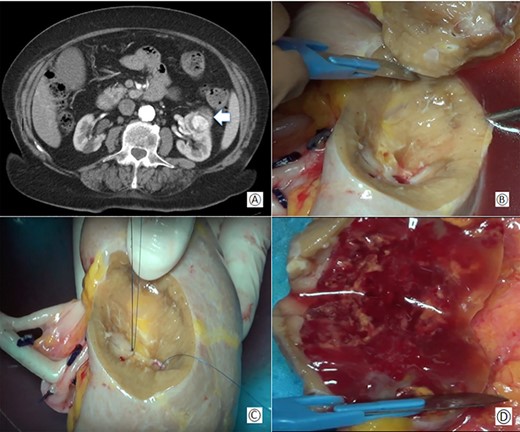

CT-scan showed a mass of 50 × 30 × 40 mm diameter in the anterior and middle region of the left kidney involving the medium calyceal group (Fig. 1A). Due to the size of the tumor and its central location, an ex-vivo PN and kidney autotransplantation was planned.

(A) Preoperative computed tomography: the white arrow shows the renal mass; (B) removal of the tumor during bench surgery; (C) suture of the renal calices during bench surgery; (D) macroscopic examination of the surgical piece.